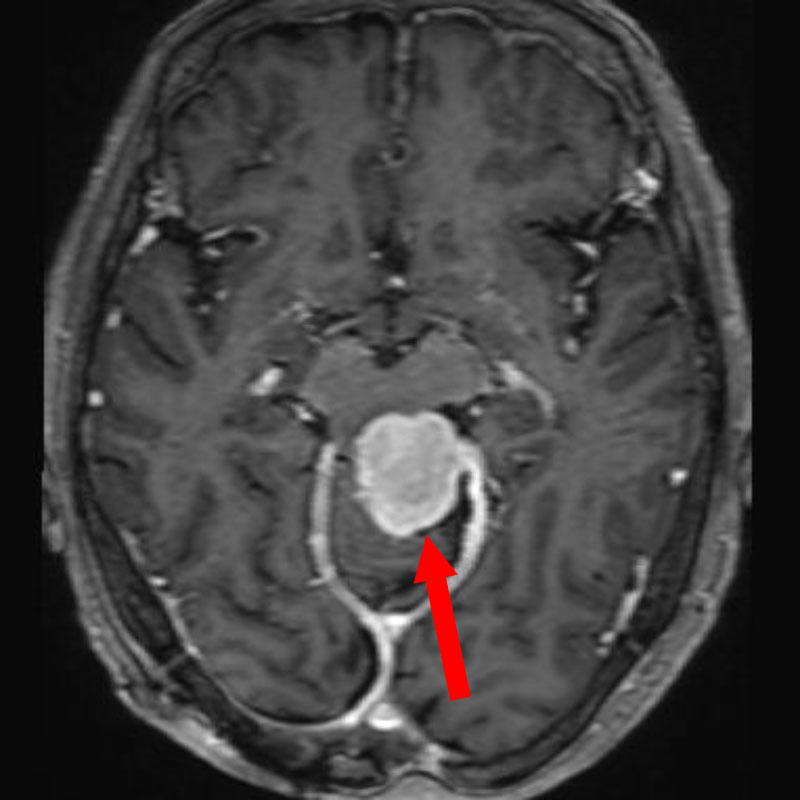

618

'25年4月

40代

小脳血管芽腫

頭蓋内腫瘍摘出術

No.’25_20 手術前1

No.’25_20 手術前2